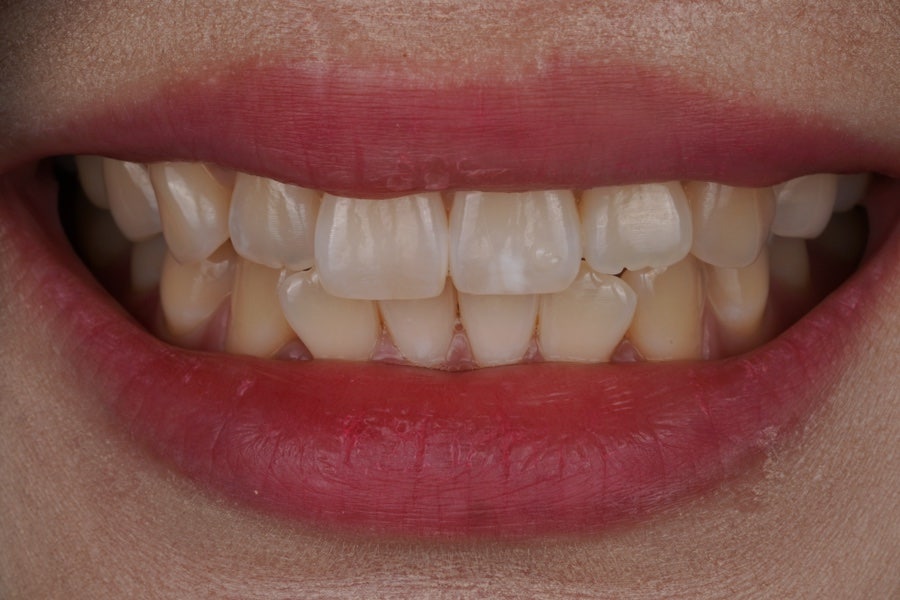

당일 치료 완료

치료가 완료된 사진인데

자연스럽게 잘 치료가 되었습니다.